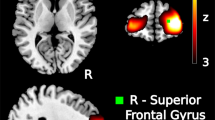

Extended Data Fig. 1 Full PTSD circuit.

(a) The peak location in the PTSD circuit was the tapetum, which connects the two hippocampi to each other. Depicted here is the peak coordinate (−12, −38, 20) (pFWE=0.035 with Westfall-Young correction for multiple comparisons) at the magenta crosshairs, a peak voxel cluster in green (pFWE<0.05, detection p < 0.001, cluster size=888 mm3), overlaid on a map with uncorrected p < 0.05 which depicts the extent of the cluster into both medial temporal lobes. (b) We identified regions that were positively correlated (yellow) and negatively correlated (blue) to lesion locations that reduce probability of PTSD. To investigate whether the positive correlations (the “PTSD+ circuit”) or the negative correlations (the “PTSD- circuit”) were more relevant, we used both to predict PTSD diagnosis in a split-half analysis. PTSD risk was independently predicted by lesion overlap with the PTSD+ circuit (Pearson r = 0.18, p = 0.01), but not the PTSD- circuit (Pearson r = 0.02, p = 0.8). Permutation testing confirmed that the PTSD+ circuit was a significantly stronger predictor than the PTSD- circuit (mean difference Pearson r = 0.14, p = 0.02). Similar results were observed when excluding patients with subthreshold PTSD (Pearson r = 0.21 vs r = 0.03, p = 0.01).